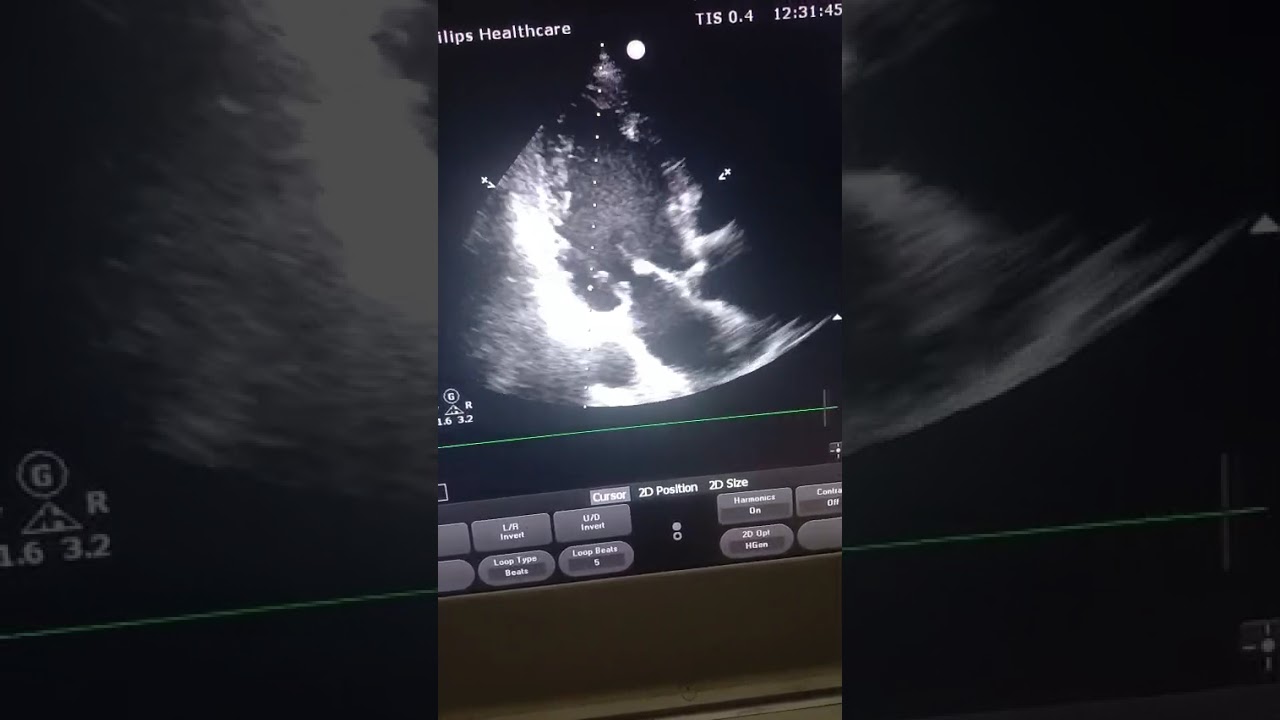

Neglected MI, markedly impaired LV systolic function and basal inferior wall aneurysm